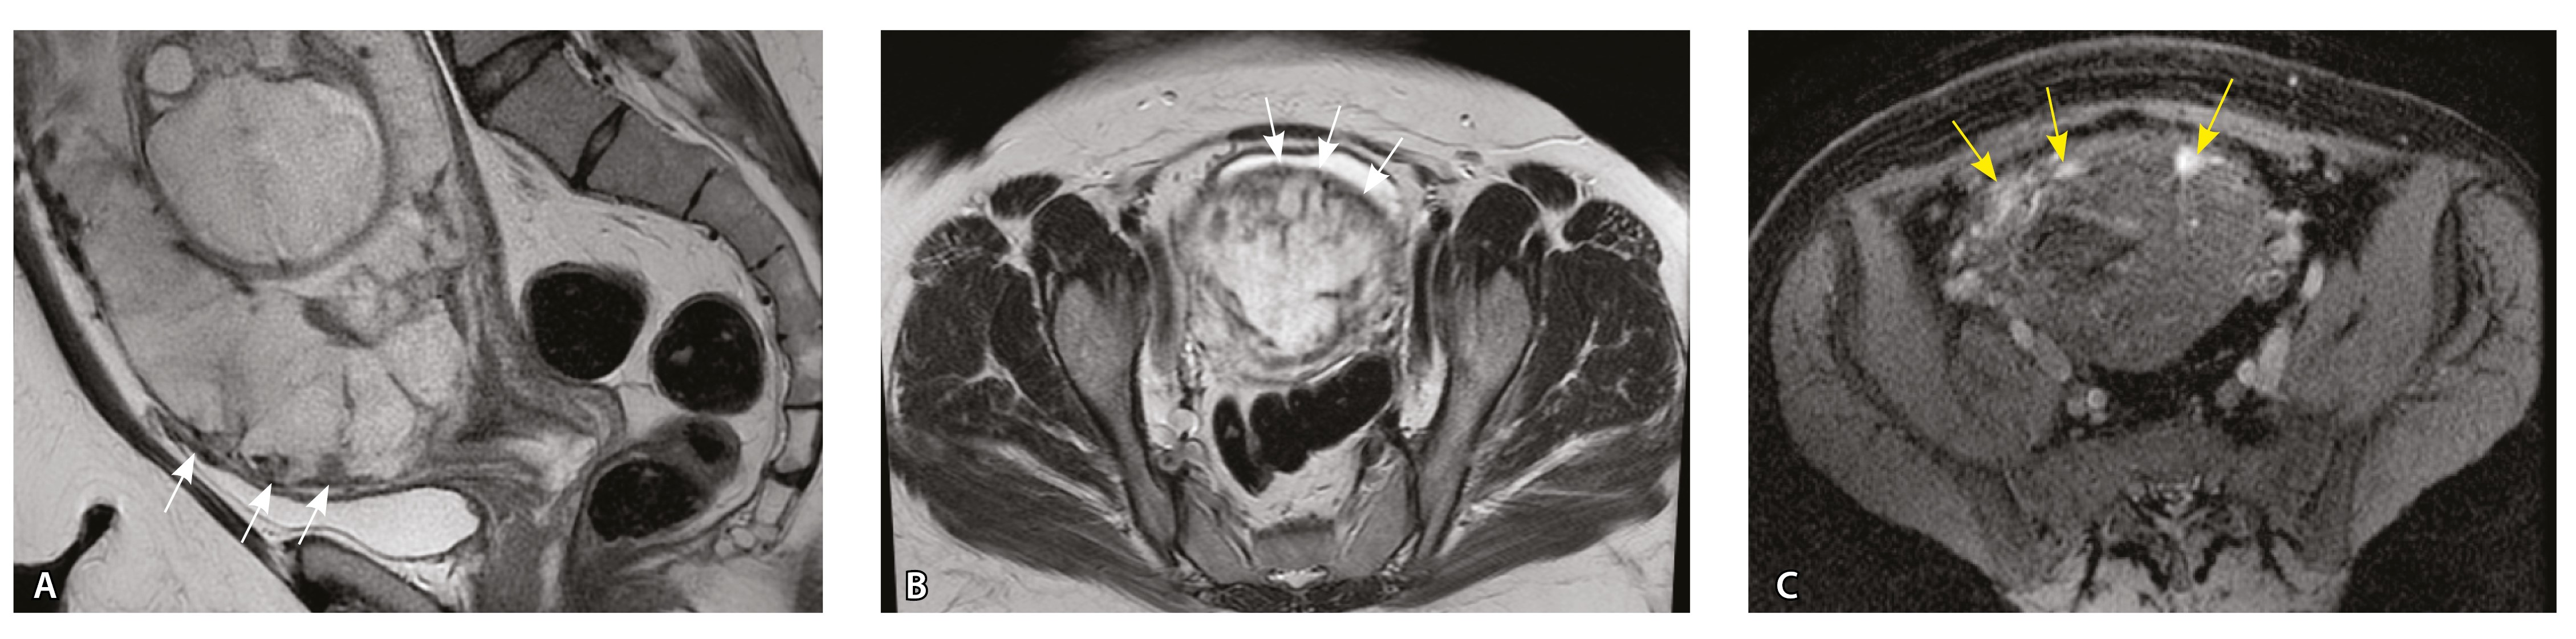

Сосуды 4-го типа. Наличие крупных извитых анастомозирующих сосудов, преимущественно по поверхности матки (в составе серозной оболочки матки) в сочетании с выраженным истончением нижнего сегмента матки (рис. 10).

Рис. 10. Беременность 33 недели, pl. percreta, PAS 3a по FIGO. На магнитно-резонансных томограммах в режиме Т2-взвешенного изображения в сагиттальной (A) и фронтальной (Б, В) плоскостях определяется внутриматочная гиперваскуляризация (желтые стрелки) и гиперваскуляризация в области выраженно истонченного нижнего маточного сегмента, с наличием многочисленных анастомозирующих сосудов по поверхности матки (белые стрелки); стенка матки в данной области представлена ретроплацентарными сосудами

Главным отличием крупных сосудов в составе серозной оболочки является то, что морфологически они находятся в пределах стенки матки. Об этом свидетельствует наличие в операционном материале тонкого поверхностного слоя мезотелия, отделяющего матку от брюшной полости (рис. 11). Его невозможно визуализировать методом МРТ из-за особенностей метода и толщины получаемых срезов.